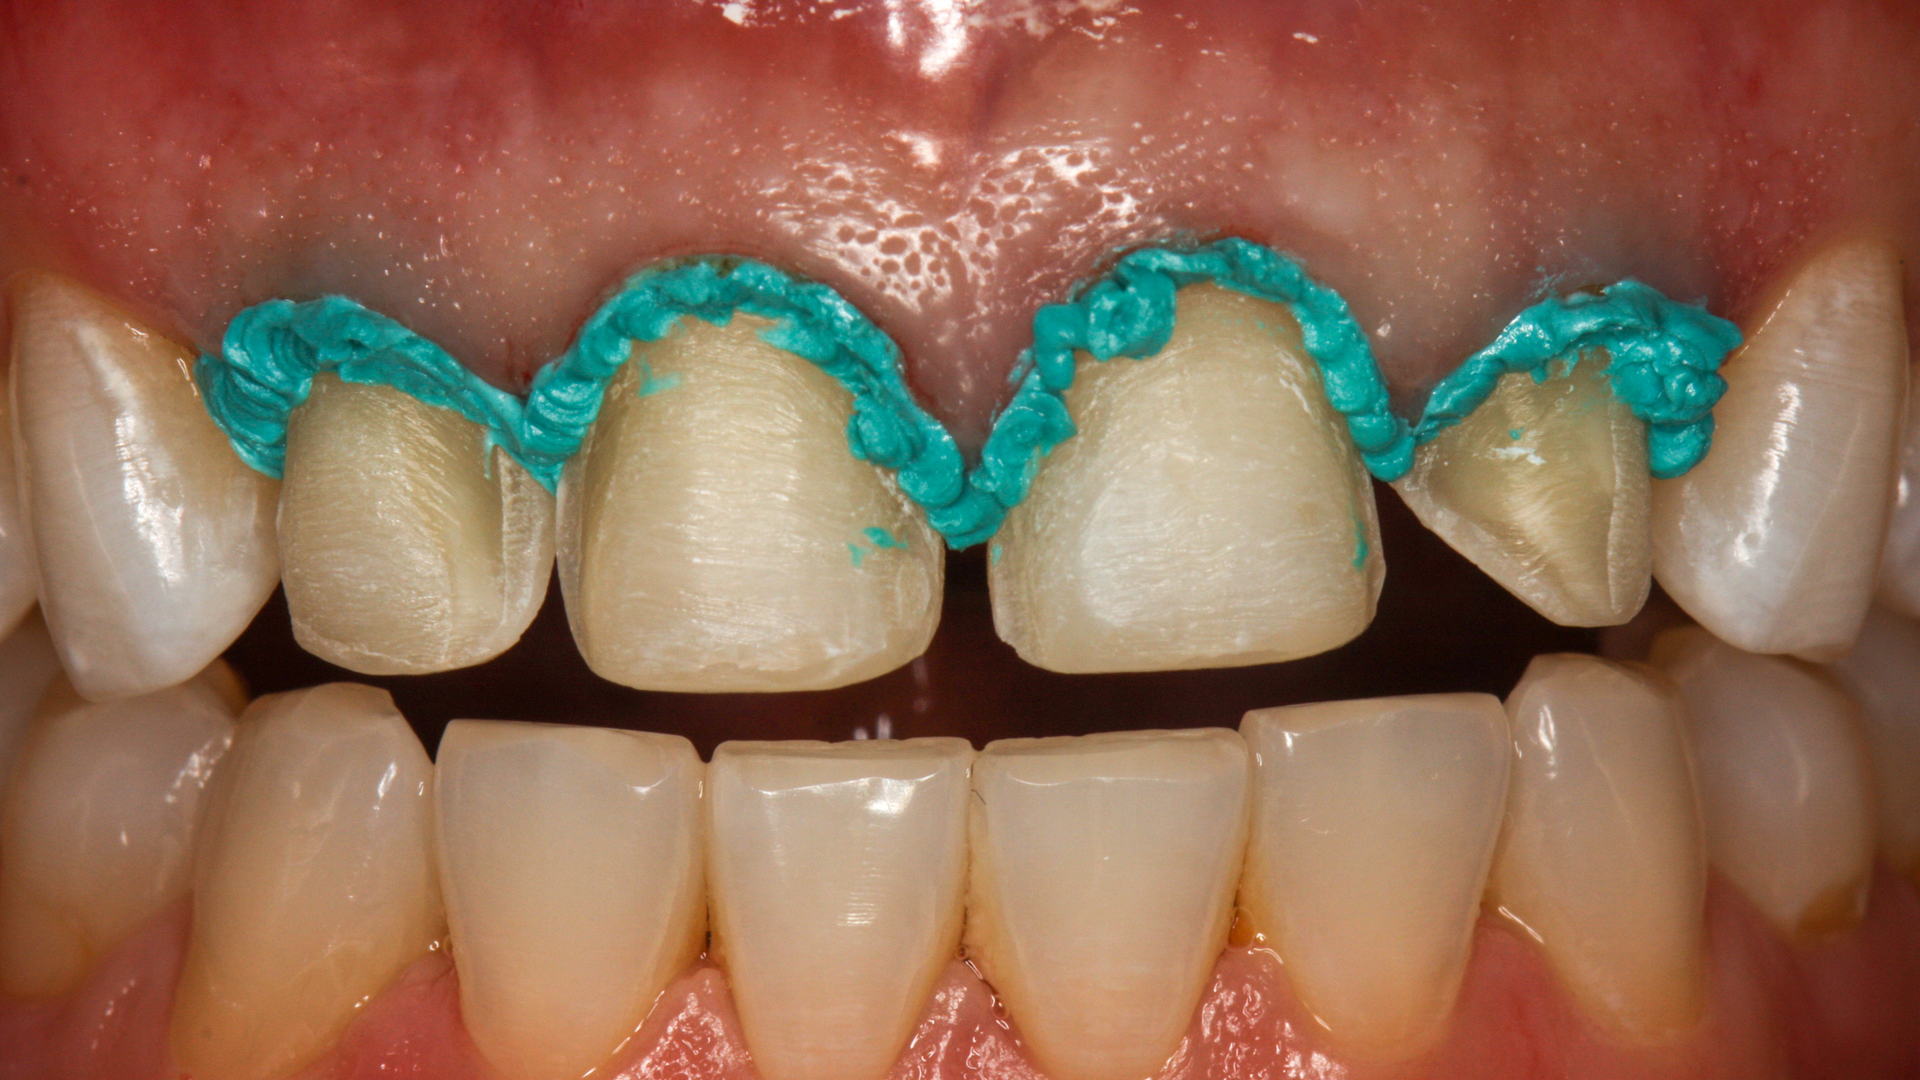

A 68-year-old patient presented with the upper right first premolar with occlusal amalgam and two distal marginal ridge fractures and discoloration under the mesial marginal ridge (figure 1). He previously had an extraction due to a fracture on his lower arch and wanted to treat the upper first premolar proactively. The existing occlusal amalgam was removed under rubber dam isolation. Caries were visualized clinically, and cracks were visualized with transillumination under both marginal ridges (figure 2). The premolar was prepared using a nonretentive cavity preparation design to allow the resin to flow in, out, and around the tooth (figure 3). Particle abrasion with 27 microns at 40 psi (PrepStart, Danville Products) was completed for microretention and biofilm removal before matrices, phosphoric acid etch (figure 4), and adhesive were placed.